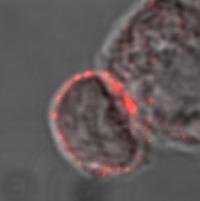

Model of the Findings: Naïve T Cells Do not Express Vitamin D Receptor nor Plc-Gamma1

image: When the naïve T cell recognizes foreign molecules with its T cell receptor (TCR) it sends activation signals (1) to the VDR gene. The VDR gene now starts the production of VDR (2). VDR binds vitamin D in the T cell (3) and becomes activated. Vitamin D bound to activated VDR goes back into the cell nucleus and activates the gene for PLC-gamma1 (5). PLC-gamma1 is produced (6) and the T cells can get started. view more

The research team was also able to track the biochemical sequence of the transformation of an inactive T cell to an active cell, and thus would be able to intervene at several points to modulate the immune response. Inactive or 'naïve' T cells crucially contain neither the vitamin D receptor nor a specific molecule (PLC-gamma1) that would enable the cell to deliver an antigen specific response.